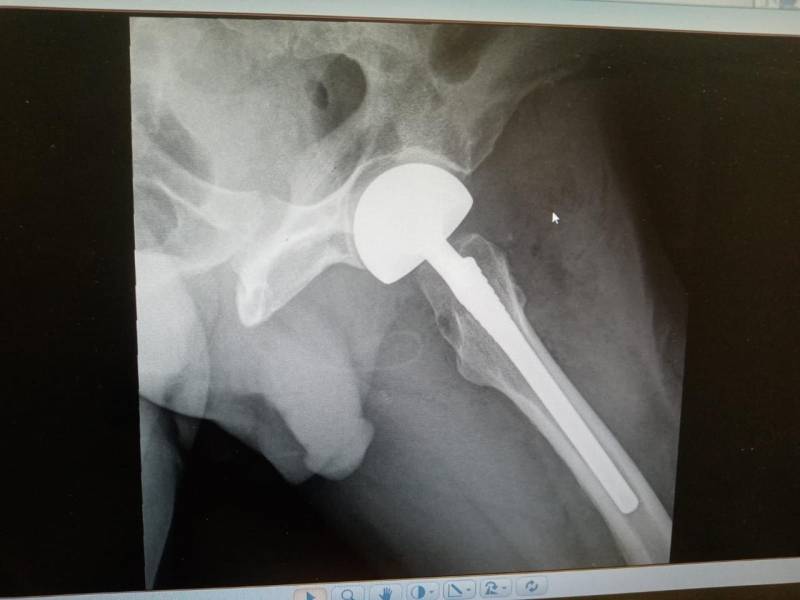

- إجراء عمليات جراحية معقدة و دقيقة في مجال العظام و المفاصل و الكسور و الإصابات ، رغم الضغط الكبير على المستشفى و أعداد المراجعين الكبيرة.

- تطبيق تقنيات جراحية حديثة و متقدمة، و ذلك في ظل التحديات التي يواجهها الفريق بسبب أعداد المرضى و المراجعين الكبيرة.

- تقديم خدمات جراحية عالية الجودة و آمنة للمرضى، رغم الضغط الهائل على المستشفى في العيادة و القسم و الطوارئ .